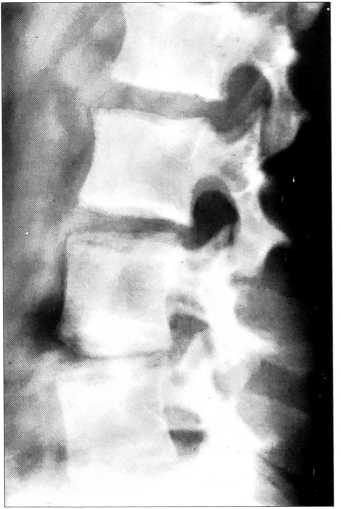

Рис. 2. Диспластическая деформация тел L1, L2 позвонков (двояковыпуклые замыкательные пластинки).

Характер изменения контуров замыкательных пластинок тел позвонков был следующим: определялись а) двояковыпуклые замыкательные пластинки и, соответственно, двояковогнутые межпозвонковые промежутки (35 больных — 14%) (рис. 2) и б) вогнуто-выпуклые замыкательные пластинки с выпукло-вогнутыми межпозвонковыми промежутками (105 пациентов — 42%). Обращала на себя внимание неравномерная толщина измененных замыкательных пластинок — истончение их контуров в вентральных отделах тела позвонка и утолщение в дорсальных, в проекции студенистого ядра межпозвонкового диска.